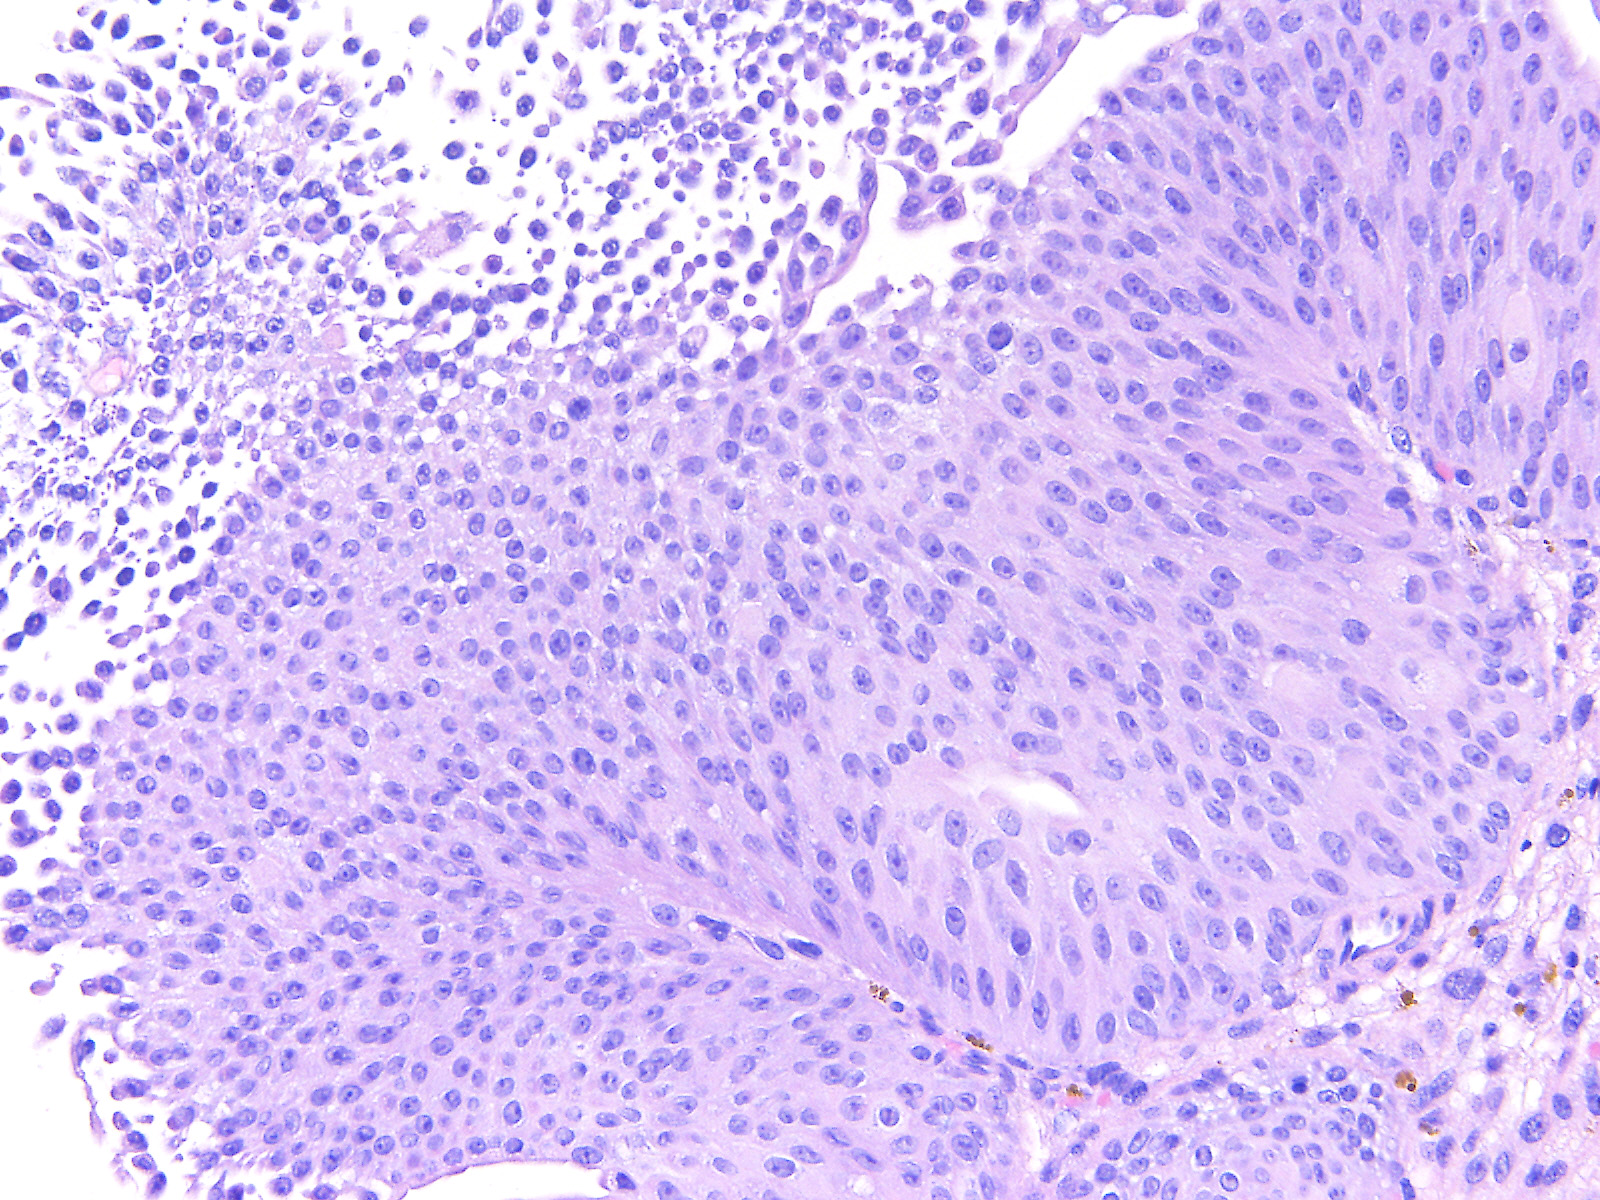

Bladder Papillary Lesions

Case ID: 559